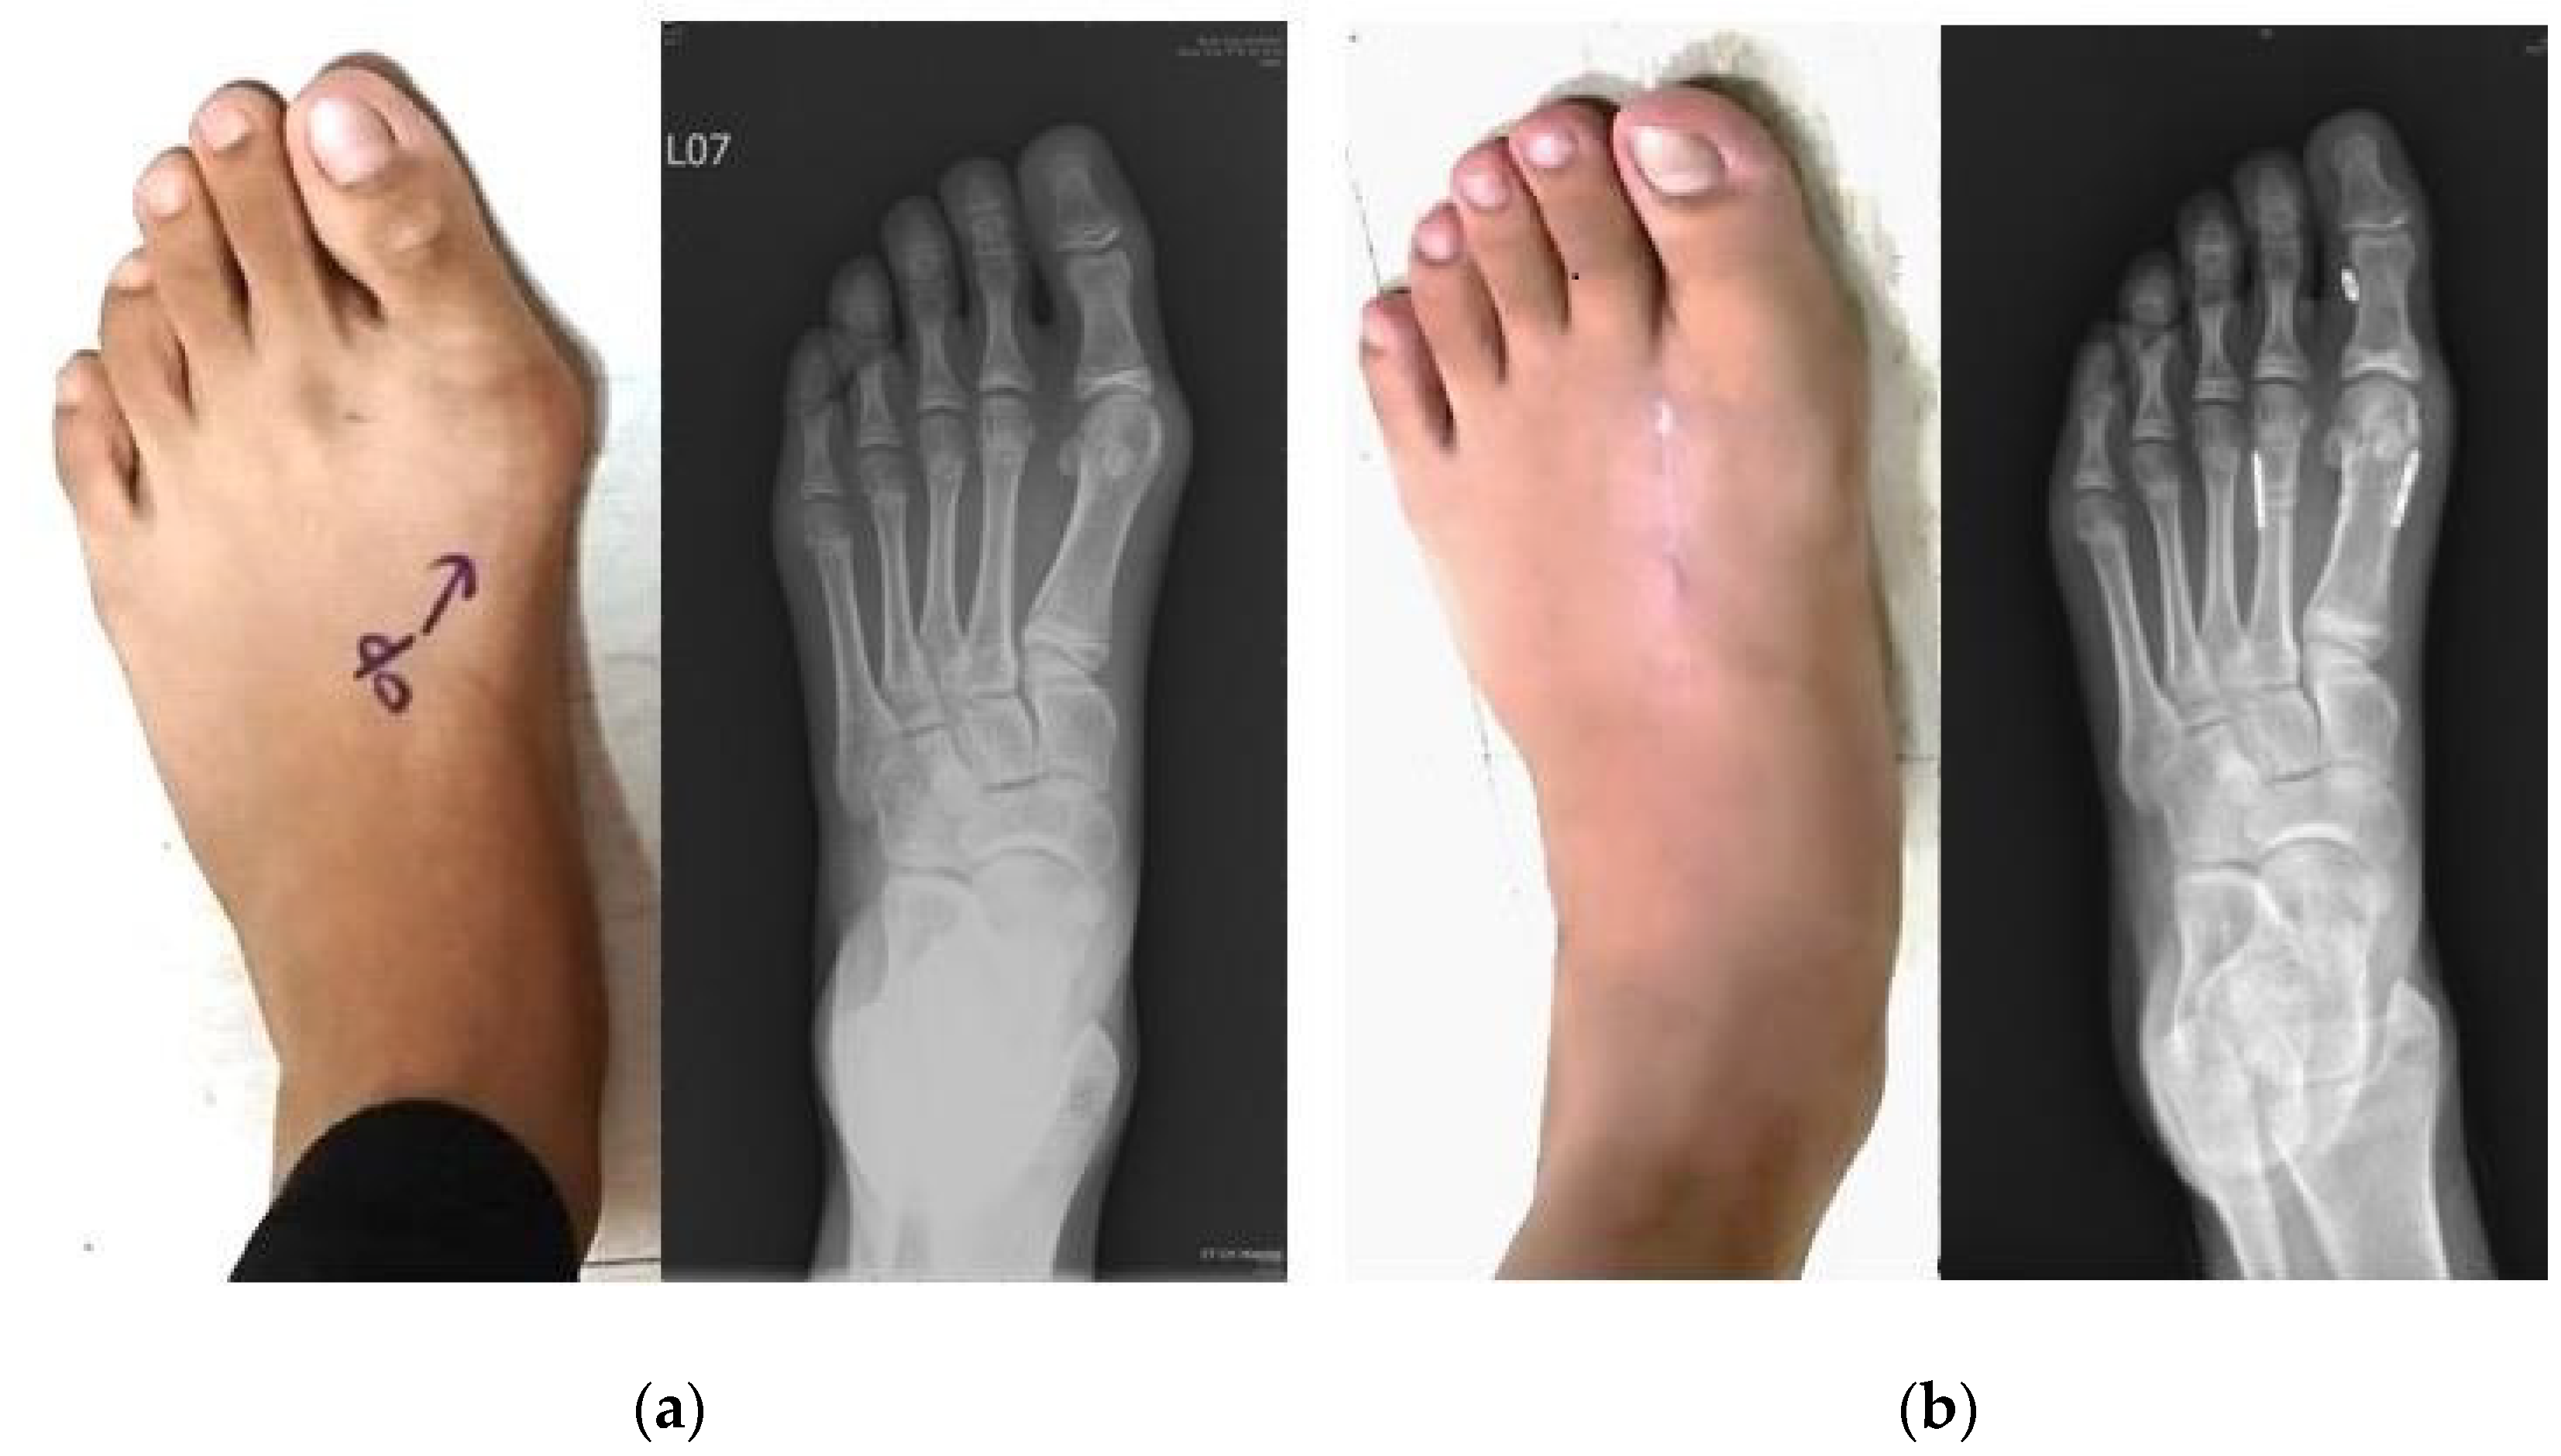

3. Results

3.1. Radiographic Outcomes